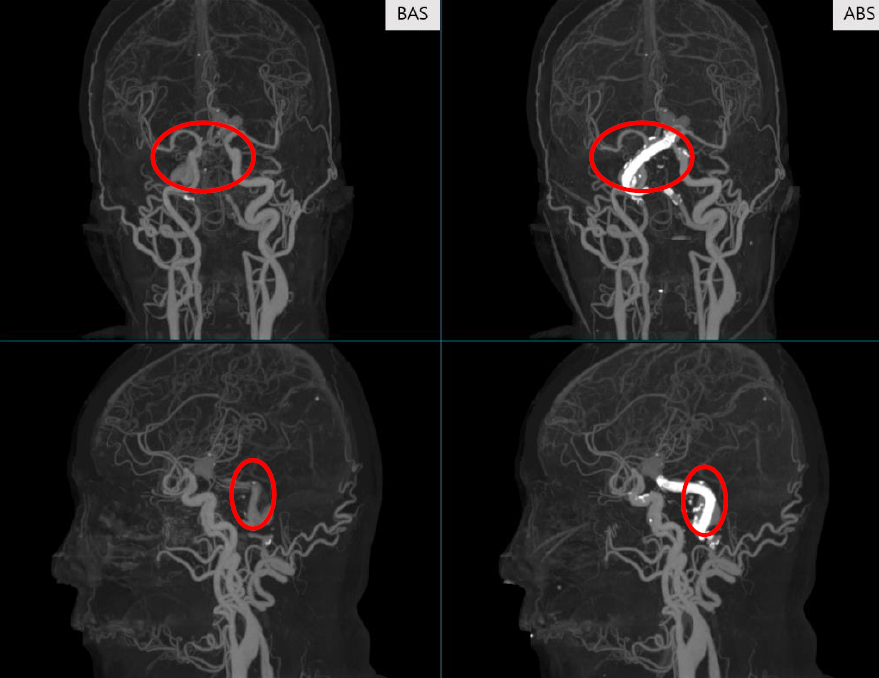

BAS(좌)와 ABS(우)의 성능 비교.

그래서 뼈만을 분할하여 조영 영상에서 직접 뼈를 제거하는 ABS (Automatic Bone Suppression) 모델이 개발되게 되었습니다. ABS 모델은 기술한 바와 같이 인공지능 모델이 뼈를 직접 제거하기 때문에 정합의 과정이 필요가 없고 따라서 우월한 성능을 보입니다.

하지만 BAS는 정합을 한다는 본질적인 문제점이 남아있게 되고 스텐트나 치아와 같이 인공물이 있어 뼈가 적절히 분할되지 못하거나, 인공 구조물로 인해 정합이 틀어질 경우 좋지 않은 결과를 보인다는 단점이 있습니다.

BAS는 기본적으로 인공지능 모델을 학습하여 개발된 알고리즘입니다. 뼈를 분할하는 과정에서 인공지능이 사용되게 되고 이렇게 뼈를 분할한 마스크를 사용하여 정합을 진행하게 됩니다.